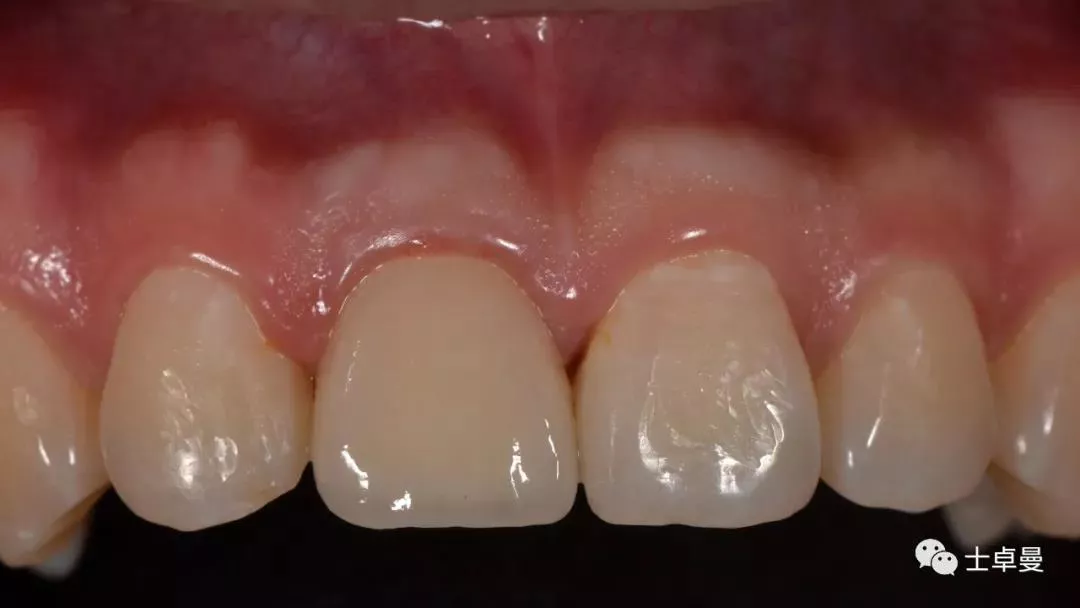

临时修复后2个月,龈缘及龈乳头位置理想,软组织健康

· 2个月后,见唇侧骨弓轮廓可,龈缘及龈乳头形态自然,去11临时修复体,植体ISQ值测定82,个性化取模,试戴Variobase氧化锆基台+LAVA氧化锆单冠,就位被动性良好,增加基台扭力至35Ncm,粘接固位上部冠,调合抛光。

完成永久修复,骨弓轮廓、龈缘及龈乳头形态自然,可见牙龈点彩,修复体外形及色泽可,患者满意。